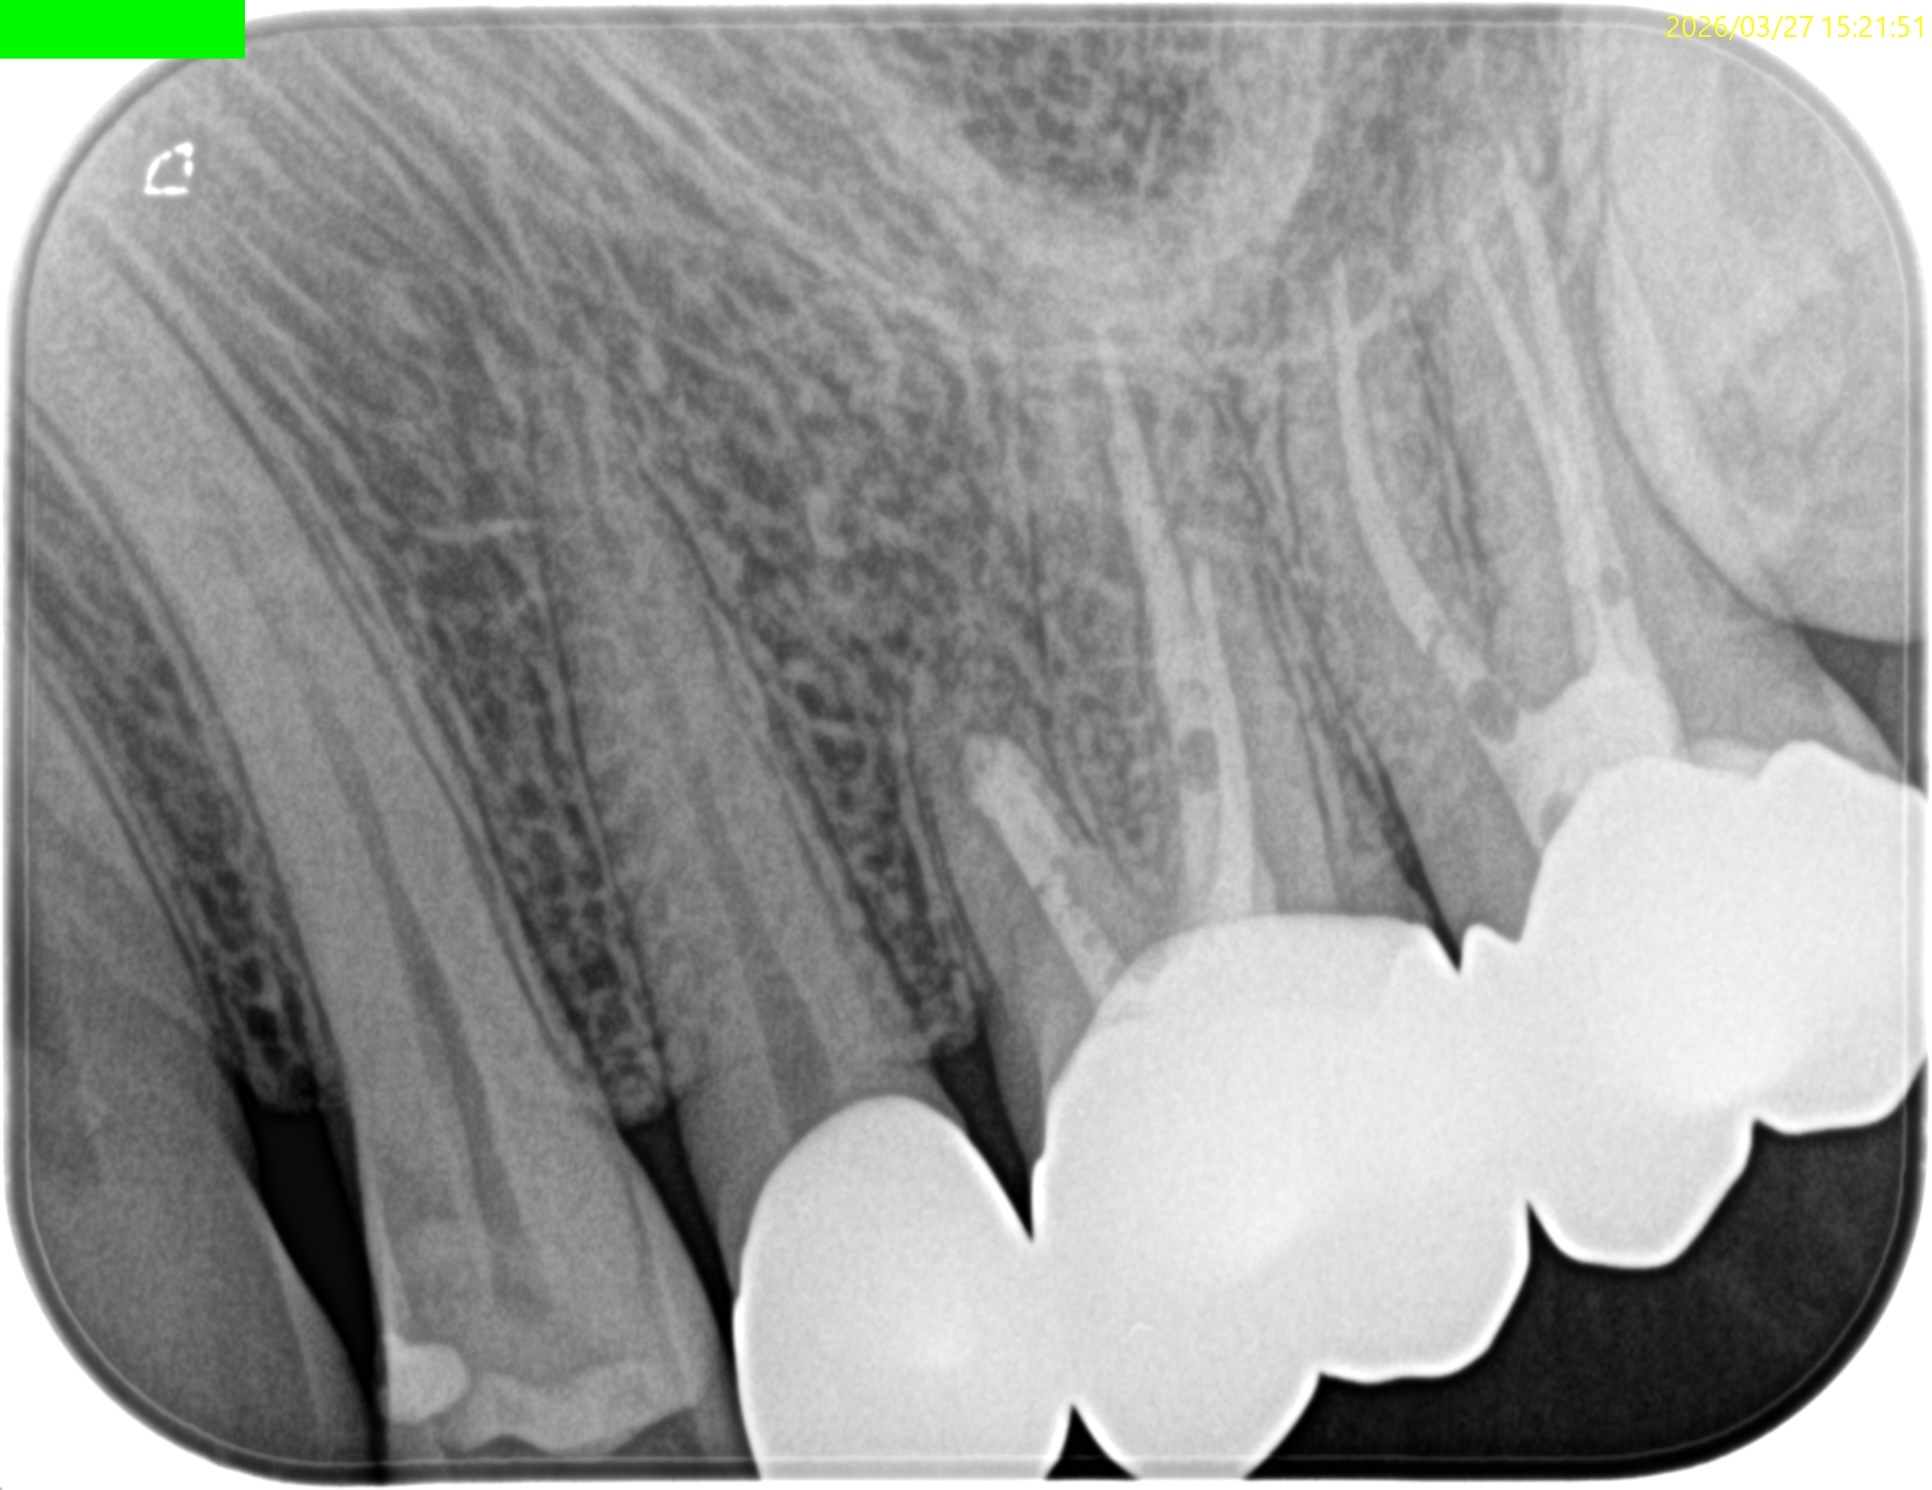

Pre-op Endo test(2025.3.31)

MB

DB

P

MBに大きな病変がある。DB,Pには病変はない。

これが検査での圧痛の原因だろう。

またすでに必要十分に拡大形成がなされていること,

MBの中央にGutta Percha Pointがあることから、MB2はなくMB1のみの処置でいいとわかるところもCBCTの強みである。

さておき、この問題を解決するには再根管治療でなく歯根端切除術であるということがわかる。